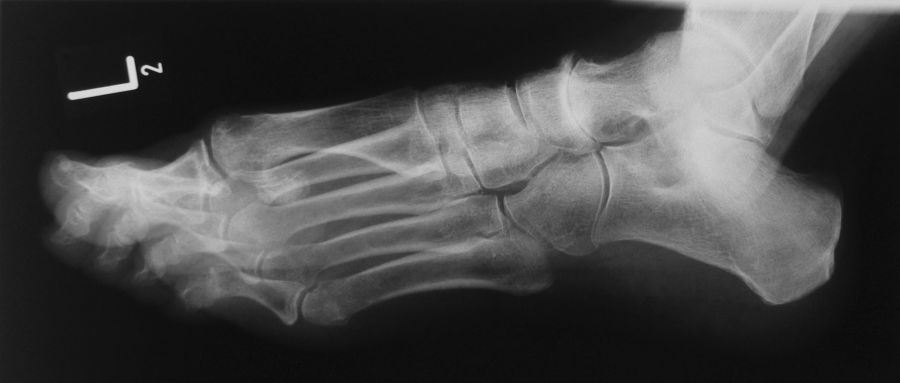

Talonavikular-, navikulocuneiforme- und calcaneocuboidale Arthrosen, also Arthrosen in der Chopart- und Bona-Jäger-Gelenklinie, zeigen sich wesentlich seltener und können in Kombination von Arthrosen aller Gelenke des Mittelfußes auftreten. Die Diagnostik beinhaltet grundsätzlich die ausführliche Untersuchung des gesamten Fußes im Stehen, im Liegen und beim Gehen. Ein Röntgenbild des Fußes im Stehen in zwei Ebenen, ergänzend eine schräge Aufnahme, sowie Saltzman und OSG-Bildgebung sind für die Diagnose und Therapieplanung essentiell. Bei Planung eines operativen Eingriffes sollte eine Computertomographie des gesamten Fußes durchgeführt werden. Zunächst sollte die konservative Therapie mittels Schmerzmedikation, Infiltration, Manueller Therapie, Einlagen, Schuh-Modifikation, Orthesen, orthopädischem Schuhwerk und ggf. eine Strahlentherapie voll ausgeschöpft werden. In zweiter Linie steht die operative Therapie. Chirurgische Eingriffe beinhalten typischer Weise die selektiven Arthrodesen der betroffenen Mittelfußgelenke. Hier wird meist die mediale Säule behandelt, die Arthrodesen der mobileren lateralen Säule sind ein Thema in der Diskussion 2.

Die Diagnostik beinhaltet die komplette klinische Untersuchung des Patienten bei entkleidetem Unterkörper mit Funktionstests, Abtasten der entsprechenden Gelenkreihen (Chopart, Bona Jäger und Lisfranc) und Überprüfung der Beweglichkeit der Tarsometatarsalgelenke mit dem Klaviertasten-Test 11. Beurteilt werden Fußformveränderungen, osteophytäre Anbauten, sowie eine mögliche Verkürzung des M. gastrocnemius-soleus-Komplexes mit Hilfe des Silfverskjöld-Tests 12. Es werdemRöntgenaufnahmen des Fußes im Stehen in 2 Ebenen und ergänzend eine Schrägaufnahme des Fußes durchgeführt. Bei Fußfehlstellungen erfolgt zusätzlich das Röntgen des oberen Sprunggelenks im Stehen und eine Saltzman-Aufnahme 13.